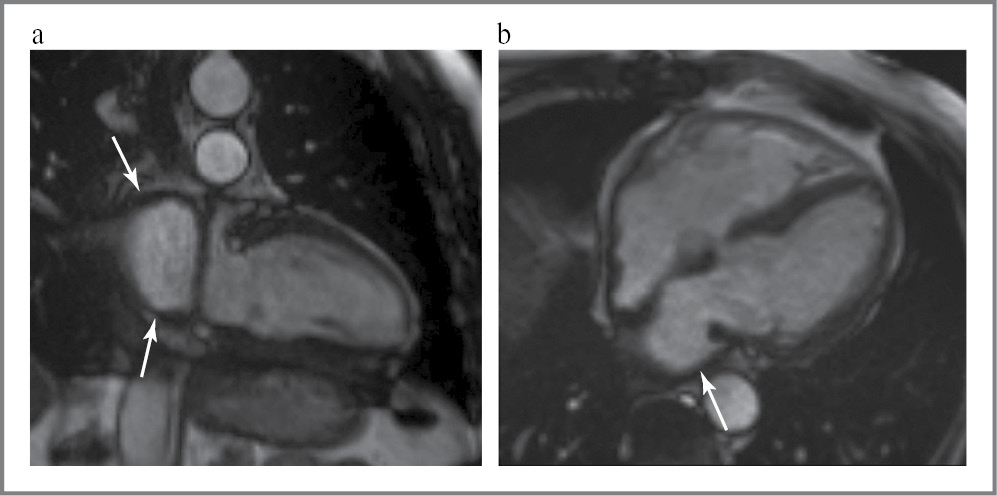

Выполнена магнитно-резонансная томография (МРТ) сердца и магистральных сосудов – визуализируется деформация левого предсердия – ЛП (состояние после ортотопической трансплантации сердца). Стенка ЛП утолщена до 4 мм в верхних отделах на уровне устьев легочных вен (рис. 4). ЛЖ небольших размеров: конечно-диастолический объем ЛЖ – 72,4 мл/м2 (N 103–192 мл), индекс конечно-диастолического объема ЛЖ – 32 мл/м2 (N 49–97 мл/м2). Правое предсердие (ПП) расширено: поперечный размер ПП – 56 мм. Данных за гипертрофию миокарда желудочков не получено. Грудная аорта имеет ровные контуры, отмечается однородный сигнал от кровотока в ее просвете. Ветви легочной артерии расширены.

Рис. 4. МРТ сердца. Кино-последовательность: а – двухкамерная длинная ось сердца, конечно-диастолическая фаза; b – четырехкамерная ось сердца, конечно-систолическая фаза. Стрелками указано деформированное ЛП с утолщенной стенкой.

Fig. 4. Cardiac MRI. Cine-MRI sequence: a – two-chamber long axis of the heart, end-diastolic phase; b – four-chamber axis of the heart, end-systolic phase. The arrows indicate a deformed LA with a thickened wall.

При кино-МРТ нарушение локальной сократимости миокарда желудочков не выявлено. Глобальная сократимость несколько снижена: фракция выброса ЛЖ ~51%.